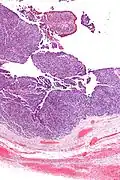

| Micrograph of transitional cell carcinoma of the ovary. H&E stain. |

Transitional cell carcinoma of the ovary (TCC of the ovary) is a rare type of ovarian cancer that has an appearance similar to urothelial carcinoma (also known as transitional cell carcinoma).[1]

TCC of the ovary is diagnosed by examination of the tissue by a pathologist. It has a characteristic appearance under the microscope and distinctive pattern of immunostaining.[2]